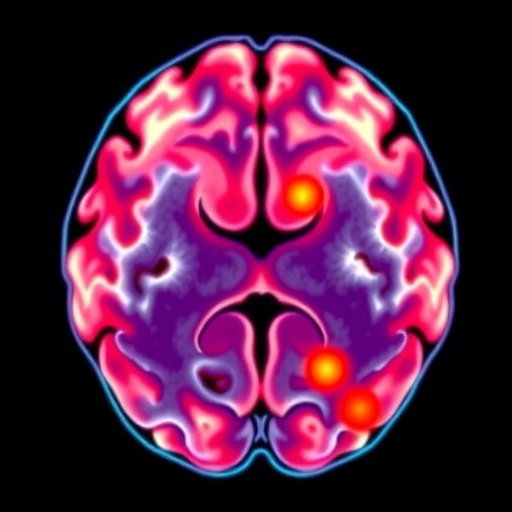

Anatomically, the cerebellum and brainstem emerged as the predominant sites for metastatic seeding, implicated in more than a quarter of cases. The frontal lobe followed as another commonly affected region. These findings bear significant implications for clinical surveillance and imaging strategies, suggesting a need for targeted neuroimaging that includes these vulnerable regions in patients with advanced ovarian cancer.